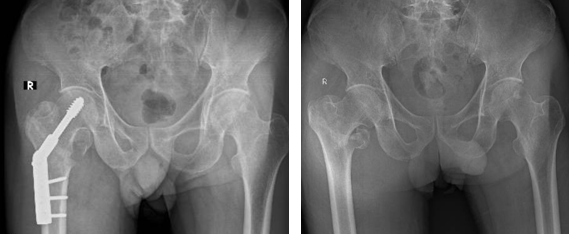

• Phương pháp kết hợp xương bằng đóng đinh nội tuỷ: Phương pháp này được chỉ định cho những trường hợp gãy xương phức tạp, gãy không vững và có thêm mảnh rời. Cụ thể, một số loại đinh nội tủy được sử dụng phổ biến gồm: Gamma, PFNA​​​​​​​

Đinh nội tuỷ PFNA

• Phương pháp kết hợp xương bằng nẹp vít: Phương pháp này được chỉ định cho trường hợp gãy xương đơn giản. Các loại nẹp được sử dụng phổ biến gồm: nẹp khóa đầu trên xương đùi, nẹp gấp góc DHS …​​​​​​​

Nẹp DHS

Nẹp khoá đầu trên xương đùi